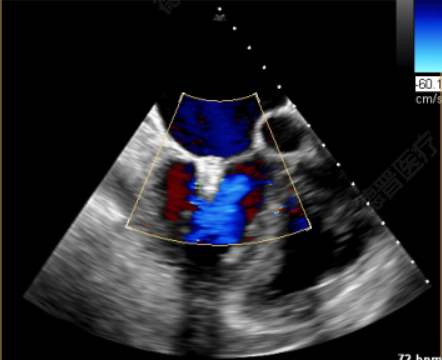

患者一术前超声

患者一术后超声

患者二术前超声

患者二术后超声